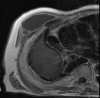

Empyema necessitans is a rare clinical finding nowadays. We report the case of a patient admitted in our ward for investigation of an unknown onset anterior chest wall mass, with no accompanying signs or symptoms. It is noteworthy that the patient had had pulmonary tuberculosis submitted to thoracoplasty more than 60 years before. Thoracic MRI showed a large heterogeneous mass, with a thick wall and internal septations located at the right anterior chest wall, as well as a heterogeneous content inside the right pleural cavity, with direct communication between both. An aspirative puncture of both masses was performed, with positive cultures for Mycobacterium tuberculosis, thus leading to the diagnosis of pleural tuberculosis with anterior chest wall empyema necessitans. A drain was inserted and antibiotics started. This case draws our attention to a very rare complication of pulmonary tuberculosis and its surgical treatment, though it aroused many decades after primary infection.